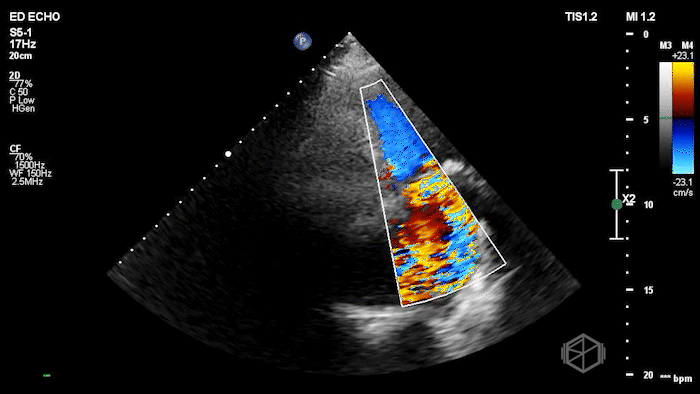

Here is the POCUS:

The POCUS shows a probably borderline LV systolic function. There is significant mitral valve calcification present. There is a mobile echodensity present near the mitral valve. On the color doppler there is severe mitral regurgitation.

In the ED, markedly elevated troponin (~42,000) and BNP 1520. Cardiology TTE revealed a 1.4 × 0.7 cm mobile echodensity on the mitral valve, concerning for papillary muscle or chordal rupture, with differential also including flail leaflet vs. vegetation, in the setting of wall motion abnormalities. The patient had a cath that showed severe triple-vessel CAD, prompting IABP placement and ICU admission. TEE confirmed severe MR due to chordal rupture with preserved LV function. She eventually did get a mitral valve replacement, but had a complex course and ultimately was made comfort care.